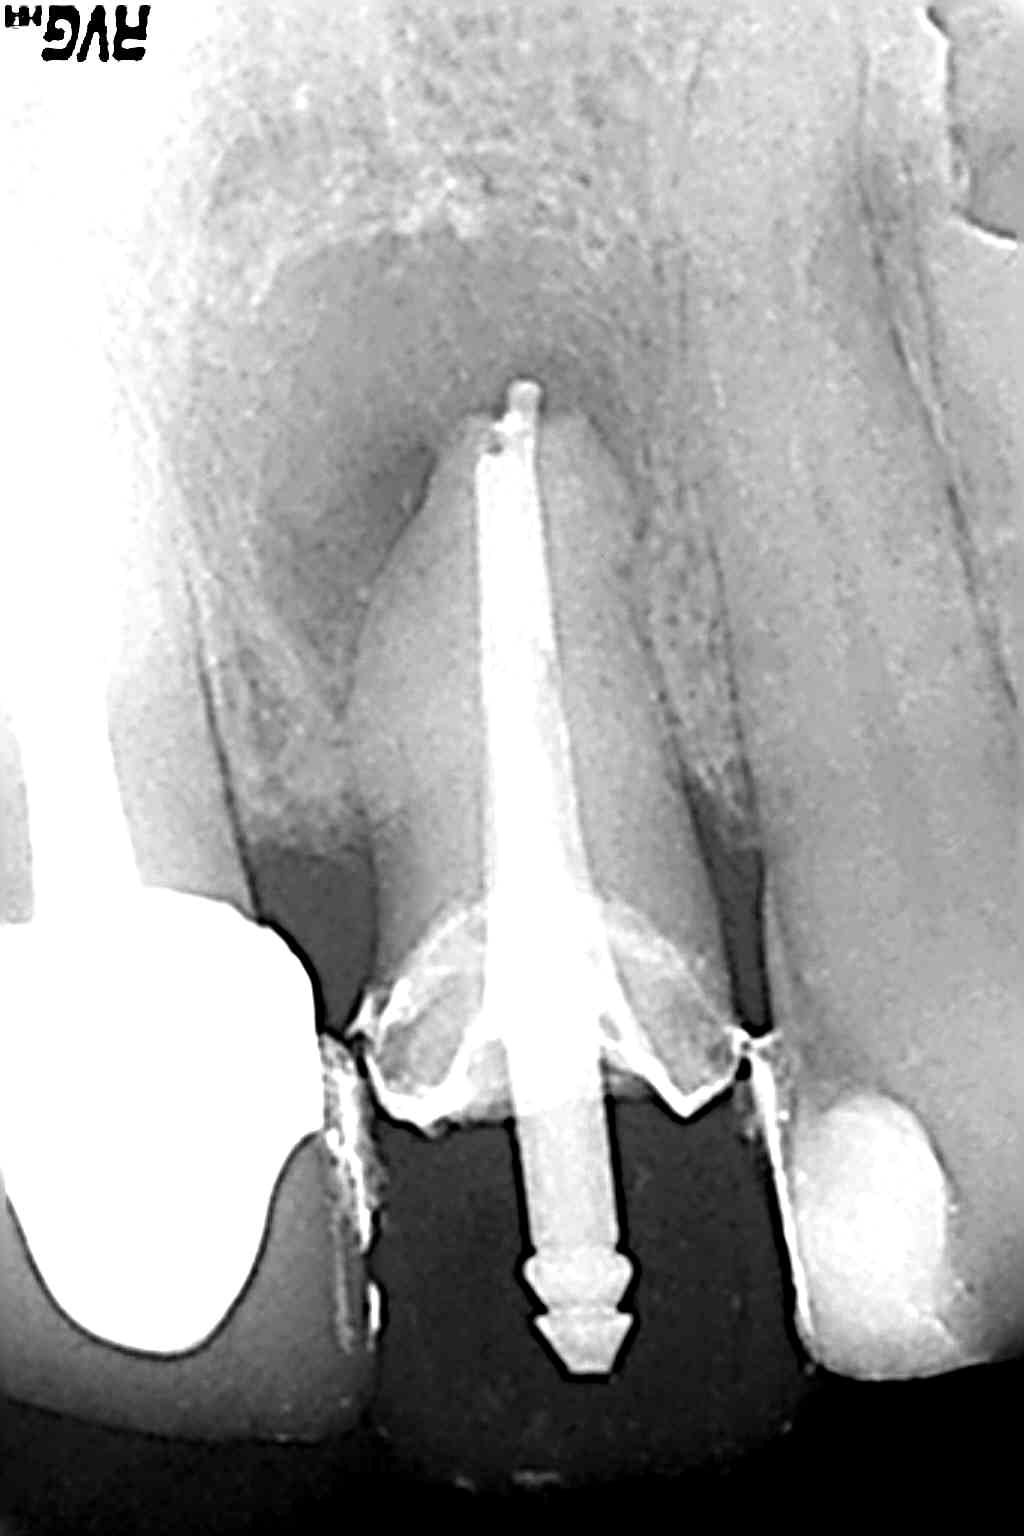

http://hpics.li/7accf64

1 : Rx avec l'ancienne Cr et la pêche.

2 : Tenon déposé (Octobre 2016)

3 : RTE (le truc blanc au bout, c'est du temp bond ... qui a fusé quand j'ai scellé ma pro la séance précedente, pour dire que l'apex était ouvert :) )